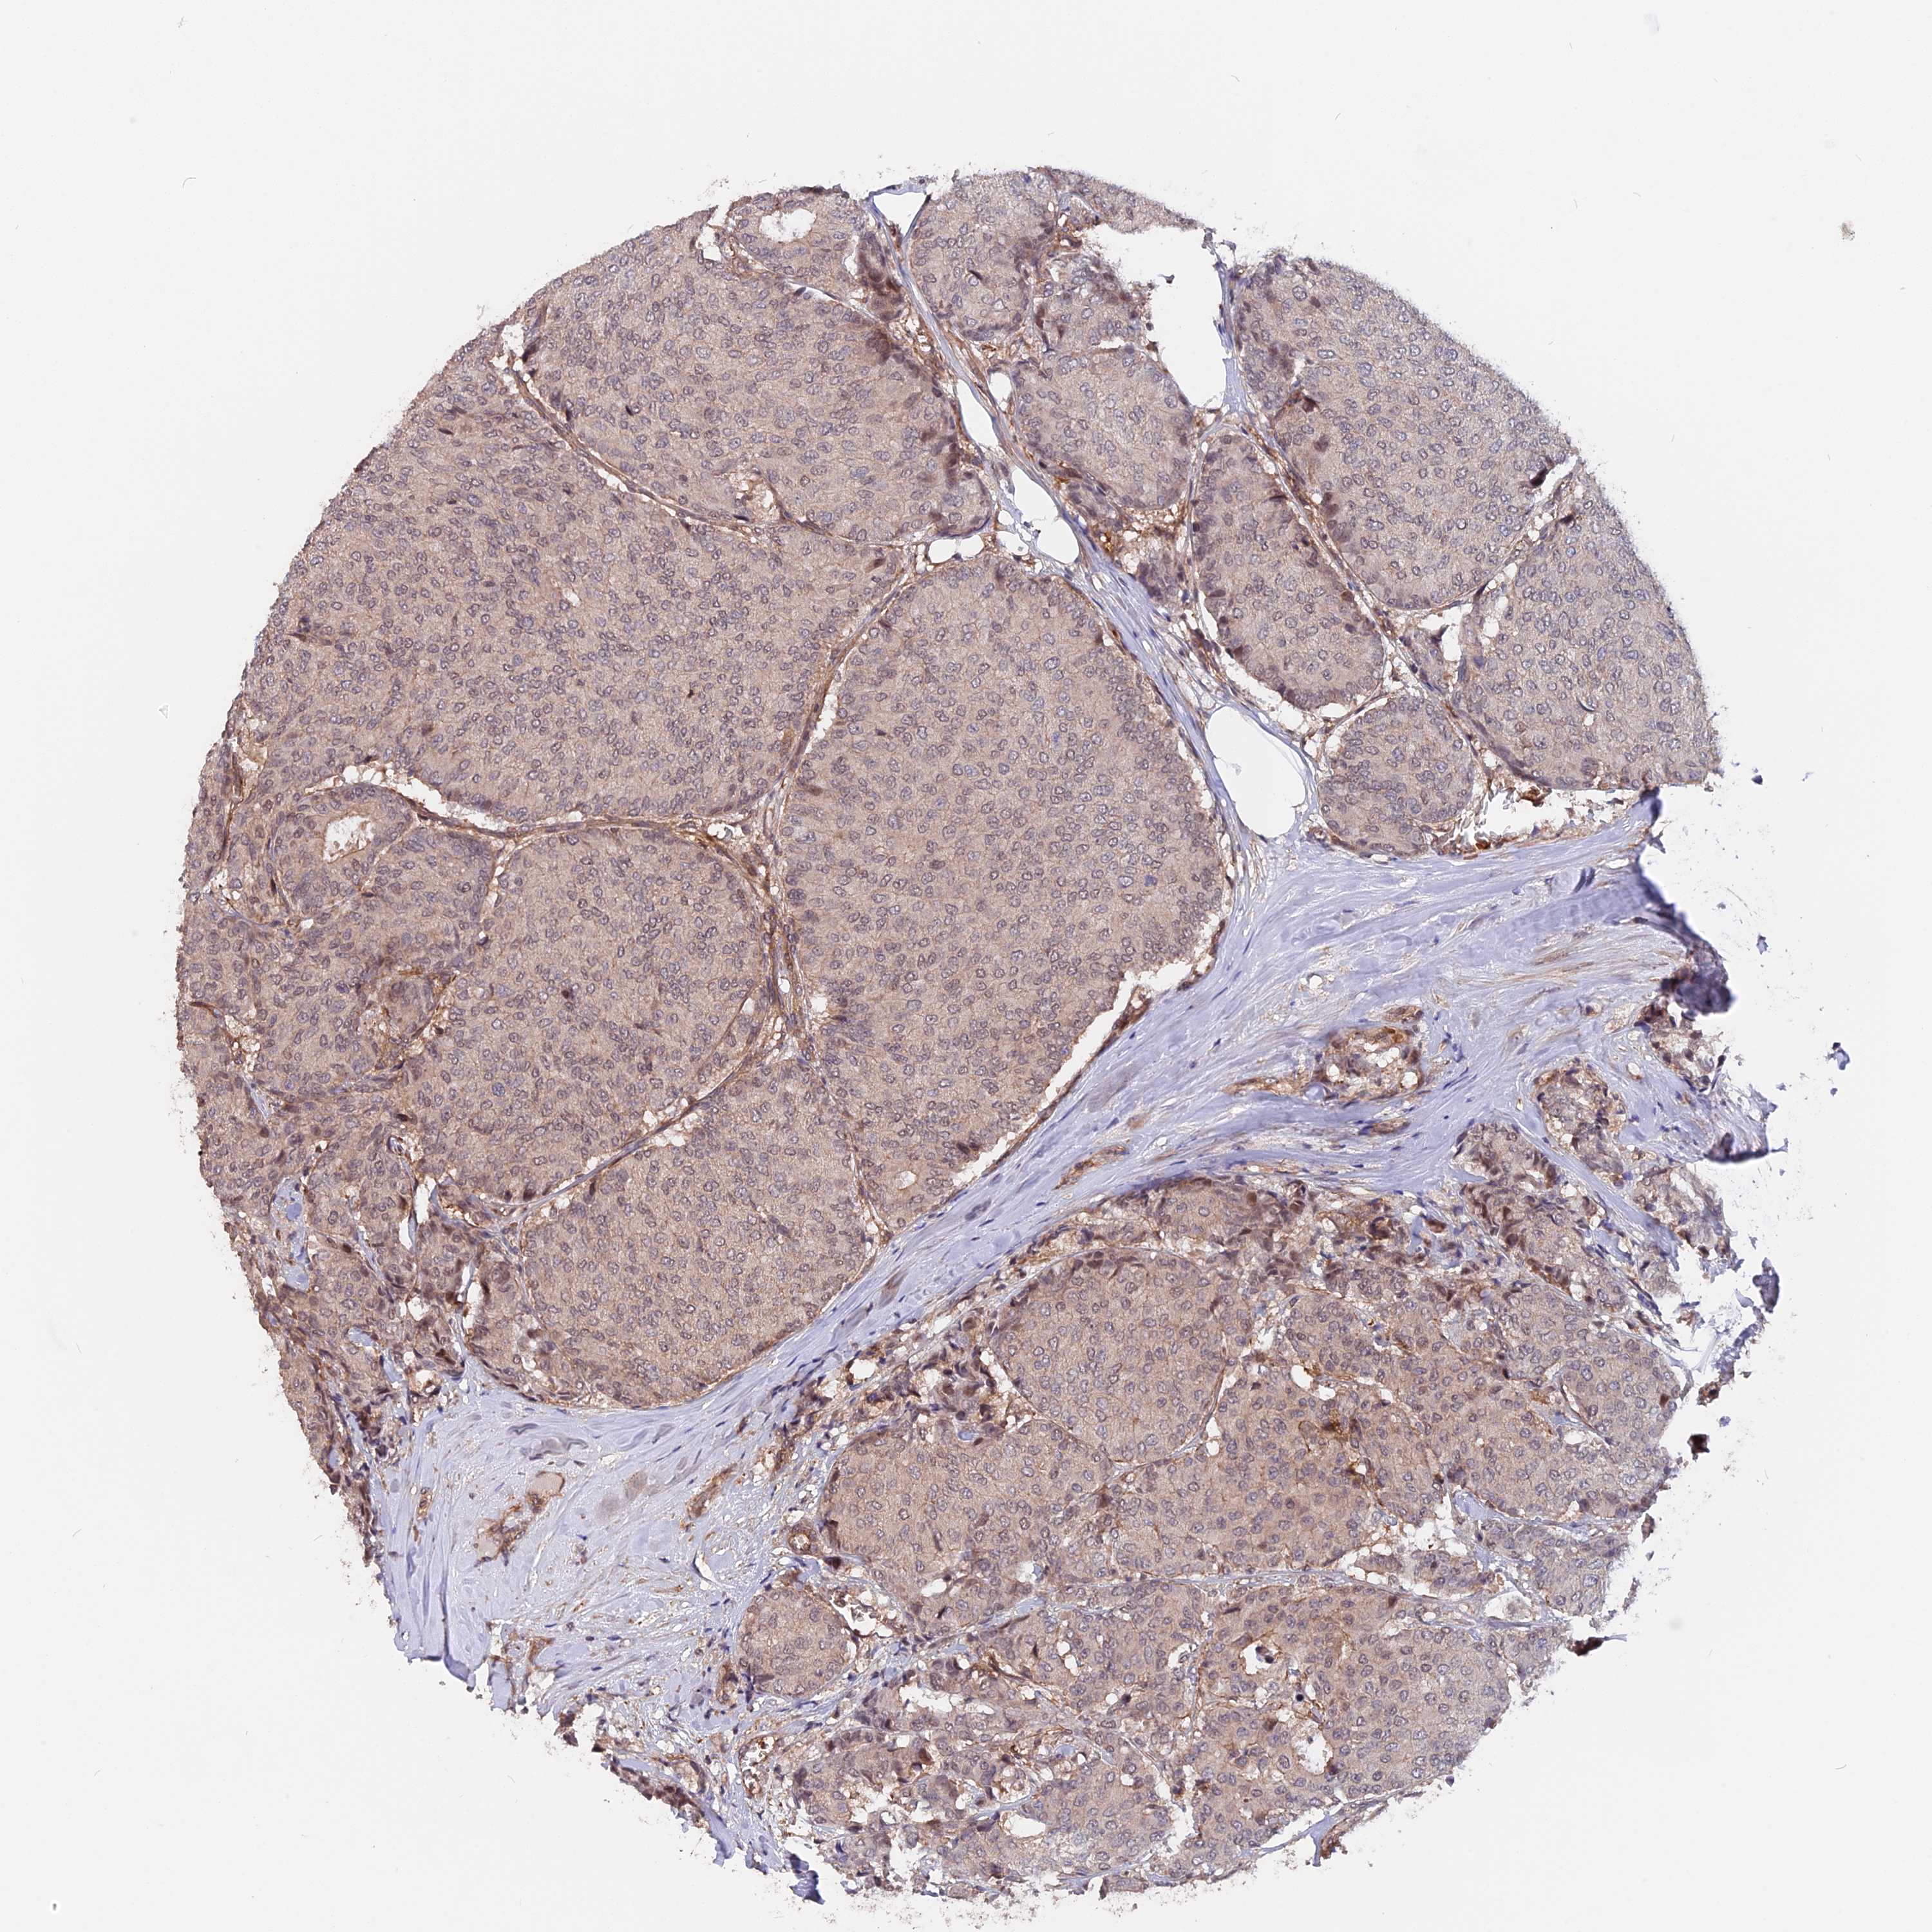

CANCER BREAST CANCER Show tissue menu

BRCA TCGA BRCA VALIDATION PROTEIN EXPRESSION

ANTIBODIES

AND

VALIDATION